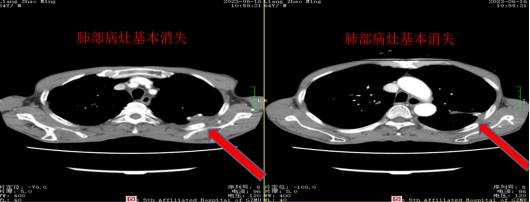

梁叔在前阶段和癌症抗衡中取得巨大胜利,越发坚定了战胜肿瘤的决心。石主任团队也根据指南以及丰富临床经验,给梁叔制定了全身巩固以及维持治疗方案,希望能够像高血压、糖尿病一样通过药物达到长期控制的效果,让梁叔同样可以和身边的同伴一样活出晚年精彩。梁叔谨遵医嘱治疗,效果显著,周围的街坊惊讶地说道,他现在这种状态,根本看不出来像个晚期癌症病人,简直太神奇了。梁叔在今年 6月最近一次复查中,病灶以及病情稳定,每天精神抖擞,吃喝玩乐,生活质量一如从前,目前无疾病进展期将近3年余。